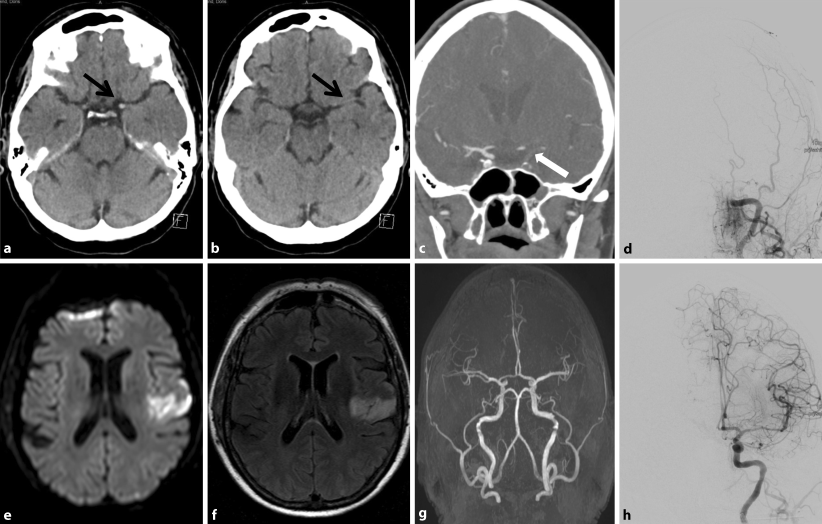

Abb. 2

Kranielle Computertomographie nativ: Dichtes Mediazeichen links (schwarzer Pfeil) ohne Frühinfarktzeichen im Mediastromgebiet (a und b). Computerangiographie mit Kontrastmittel: Karotis-T-Verschluss links (weißer Pfeil) (c). Katheterangiographie: Verschluss der distalen A. carotis interna (d), mechanische Rekanalisation mit vollständiger Rekanalisierung TICI 3 (h). Kranielle Kernspintomographie postinterventionell: ischämischer mittlerer Mediateilinfarkt links (in Diffusion e und in FLAIR f). Intrakranielle Kernspinangiographie 3d-TOF: Rekanalisierung der A. carotis interna links mit unauffälligen Flusssignalen in den Arteriae cerebri mediae und anteriores ohne Stenose (g)

In der kraniellen Computertomographie (cCT) zeigte sich nativ ein hyperdenses Mediazeichen links ohne Frühinfarktzeichen. In der ergänzenden Computerangiographie mit KM (CTA) kam ein Karotis-T-Verschluss links zur Darstellung. Es erfolgte 110 min nach Erstauftreten der Symptome nach Ausschluss von Kontraindikationen eine körpergewichtsdosierte systemische Lyse mit rt-PA. Zeitgleich wurde die Patientin für eine Neurointervention vorbereitet. Katheterangiographisch zeigte sich bereits extrakraniell ein etwa 4 cm langer Verschluss der A. carotis interna (ACI) links. Hier gelang unter Aspiration eine vollständige Rekanalisierung (TICI 3) des vorderen Versorgungsgebietes links (Abb. 2).

Am ersten postinterventionellen Tag beklagte die Patientin geringe Wortfindungsstörungen und eine leichte faziale Parese rechts mit Feinmotorikstörung des rechten Arms (NIHSS 2). Das neurologische Ergebnis der Patientin 90 Tage nach Ereignis stellte keine wesentlichen Einschränkungen im Alltag dar (mRS 1). Als Sekundärprophylaxe bei kardioembolisch bedingtem Schlaganfall erhielt die Patientin eine direkte orale Antikoagulation.